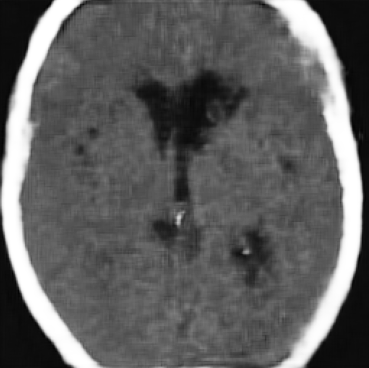

The former is a randomised-controlled trial that collected brain imaging data, primarily CT scans, from 3035 patients exhibiting stroke symptoms. The scans were conducted at two time points: immediately after the patients’ hospital admission and again between 24-48 hours later. Radiologists involved in the trial assessed the presence or absence of early ischemic signs and recorded the location of any identified lesions for positive scans. In our analysis, we considered a total of 5681 scans, of which were classified as negative (no lesion), while the remaining scans were positive. In particular, We considered 11 slices for each scan and resized each slice to . For more detailed information about the trial protocol, data collection, and the data use agreement, please refer to the following URL: IST-3 information.

As annotations of lesions are not available in IST-3, we utilise this dataset primarily for qualitative evaluations. On the other hand, for the BraTS2021 dataset, we have access to lesion annotations, enabling us to conduct quantitative analysis of the anomaly maps that we create. Both datasets were divided into training, validation and test sets with a 70-15-15 split.

4.3 Counterfactual Examples

In Figures 2 and 4 we display examples of healthy images and anomaly maps obtained with the different approaches. We can observe that f-Ano GAN is not able to generate credible counterfactuals and generally produces images of poor quality and unrealistic appearance. On the other hand, the approaches based on diffusion models are able to create more high-quality results. However, the ones obtained with CG and CFG seem to present some artifacts, which may not only impact the realism of the counterfactual examples but also the precision of the anomaly maps obtained from them. In order to better quantify the capability of these methods to accurately segment pathological areas, we compute the Dice scores of the anomaly maps they generate.